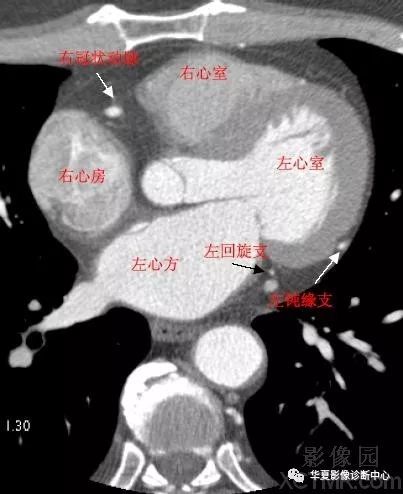

影像解剖|心脏冠状动脉ct解剖中文详细标注(图文)